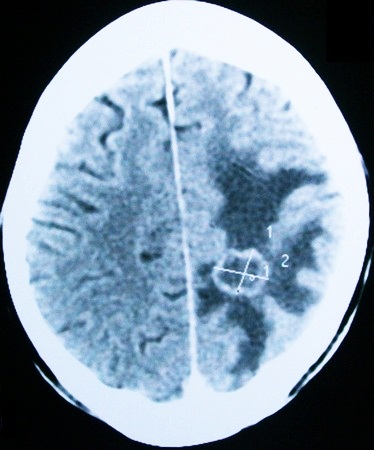

Для диагностики заболевания используются различные современные методы: МРТ, КТ, УЗИ и многие другие. Если форма патологии не молниеносная, то заподозрить наличие заболевания может невролог, который отметит прогресс ухудшения состояния больного, наращивание процессов нарушения сознания вместе с симптоматикой менингита.

Чтобы подтвердить диагноз, используются методы магнитно-резонансной и компьютерной томографии.

Люмбальная пункция выполняется далеко не во всех случаях, потому что есть определенная опасность, что церебральные структуры в результате развивающегося отека сменили свое местоположение одновременно со сдавливанием ствола. Также помогают в постановке диагноза: биохимия крови, сбор анамнеза, анализ неврологического статуса, нейровизуализирующие обследования.

Учитывая тот факт, что отек головного мозга вызывает серьезные осложнения, а сам пациент зачастую нуждается в неотложной помощи, диагностирование должно отнимать минимальное количество времени. Диагностика выполняется в условиях стационара с одновременным проведением всех необходимых терапевтических мероприятий. После больного помещают в реанимацию или интенсивную терапию.